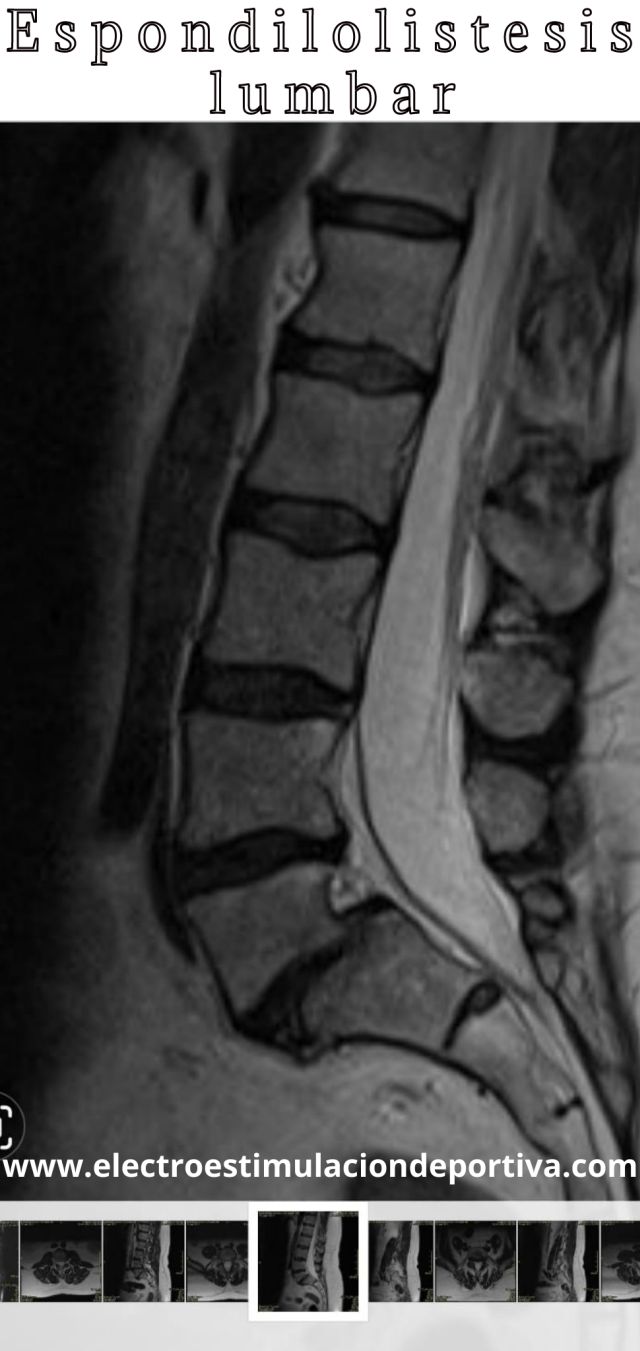

La espondilolistesis lumbar es el desplazamiento de una vértebra hacia delante.

En mi caso la lesión está en la L5, y va acompañada de rotura parcial de la vértebra (espondilolisis)

Por lo general las vértebras lumbares L4, L5 y S1 son las más afectadas debido a que soportan más carga mecánica, aunque puede aparecer también la espondilolistesis en la zona cervical.

Hola Pedro, hace unos 4 meses me hicieron una TAC y se identifican signos de anterolistesis grado 2 de L5 sobre S1. Esta espondilolistesis la L5, y va acompañada de rotura parcial de la vértebra (espondilolisis). La foto de tu columna es igual a la mia, tengo 52 años y la rotura se produjo en el gimnasio con una mala tecnica haciendo peso muerto, ahora no quiero operarme, el dolor es lumbar y se extiende por la pierna derecha, si bien es soportable es cronico y me quita calidad de vida. Hice fisio, hago RPG, sigo entrenando en GYM con ejercicios “permitidos” como indicas en tu articulo. Estoy con una entrenadora que me cuida pero el dolor sigue y es constante en determinadas posiciones de extension (parado o caminando). No quisiera ni operarme ni pasar el resto de mi vida con dolor , que crees que pudiera hacer para hacer desaparecer el dolor ? Gracias !!